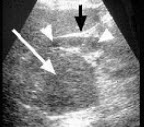

11、单项选择题

某患者阴囊增大,自诉用力时阴囊可增大,平卧缩小,无外伤史。B超检查超声声像图如下,最可能的诊断为()

A.鞘膜积液

B.附睾炎性包块

C.斜疝

D.附睾结核

E.股疝